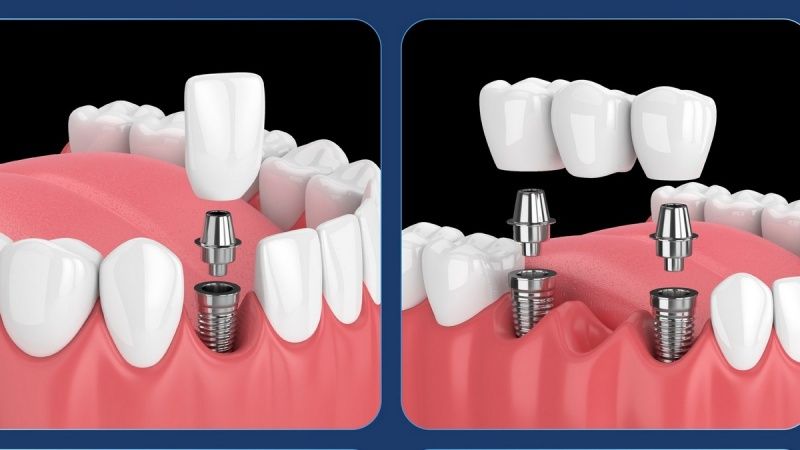

Implant Tekka Pháp nổi bật với công nghệ xử lý bề mặt SA (Sandblasted and Acid-etched), giúp tăng độ nhám vi thể và diện tích tiếp xúc với xương, từ đó tăng khả năng tích hợp xương nhanh chóng và giảm thời gian lành thương.

Bên cạnh đó, thiết kế ren xoắn kép cùng thân trụ thuôn nhẹ giúp trụ bám chắc ngay từ khi cấy, tạo độ ổn định sơ khởi cao, phù hợp cả với những trường hợp xương yếu hoặc cần phục hình tức thì. Đây là một trong những điểm mạnh giúp Tekka trở thành lựa chọn ưu tiên trong các ca trồng răng Implant hiện đại.